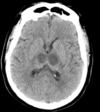

Quando começa o efeito de massa da hipodensidade corticossubcortical no AVCi visto pela TC?

A

Pico no 3 - 4 dia. O tempo de AVCi agudo 24h - 7 dias é marcado pela acentuação da hipodensidade e pelo efeito de massa positivo, que muitas vezes necessita de craniectomia descompressiva.

Artéria cerebral média hiperdensa Perda da diferenciação da substância branca com a cinzenta - Apagamento do núcleo lentiforme e sinal da fita insular Hipodensidade do parênquima Edema (apagamento de sulcos corticais de forma assimétrica).